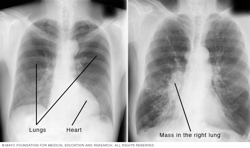

Chest X-ray

A chest X-ray helps detect problems with the heart and lungs. The chest X-ray on the left is typical. The image on the right shows a mass in the right lung.